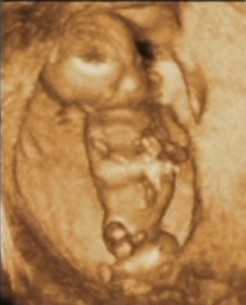

írta:kobzoszsuNyulasz![]()

Nagyon aranyos ez az ugráló nyulasz.